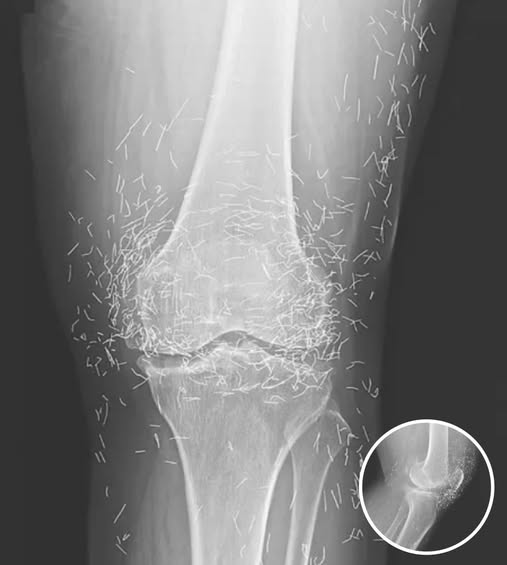

A routine X-ray revealed an unexpected surprise when doctors examined the knees of a 65-year-old woman suffering from severe joint pain. What they found was nothing short of astonishing — hundreds of tiny gold needles embedded deep in her tissue.

A X-ray of the patient’s knee showing acupuncture needles embedded in the tissue, Photo Credit: Reddit

As for the South Korean woman, her case was recently documented in the New England Journal of Medicine. While the needles may have been intended to help, her X-rays tell a cautionary tale about the potential risks of extreme alternative therapies.